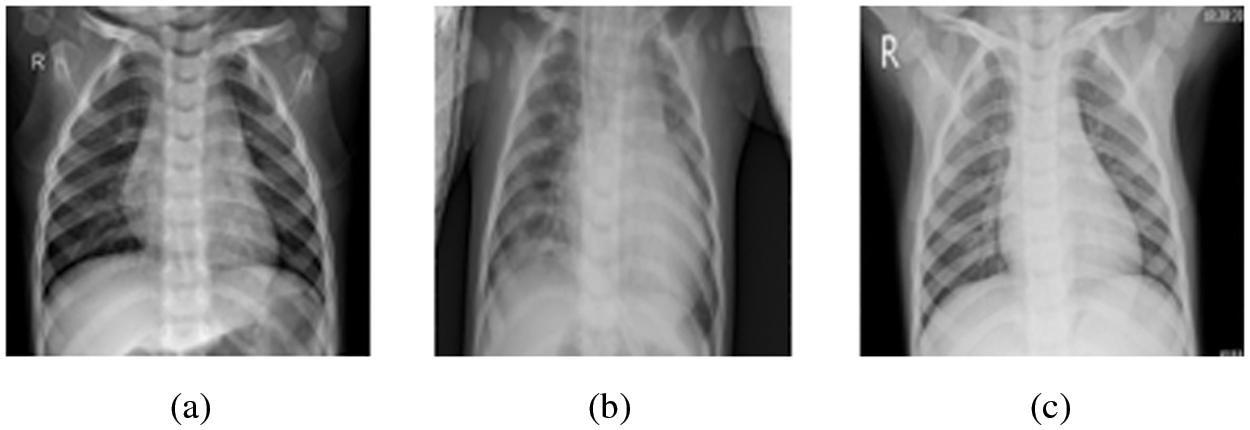

The pneumonia images utilized in this research were taken from Kaggle’s pneumonia dataset, which contains 5247 images with resolutions between 400 and 2000 pixels [36]. Tab. 2 shows that 3906 of the 5247 chest X-ray pictures (2561 bacterial and 1345 viral) were taken from patients with pneumonia, while 1341 images were taken from healthy people. Some cases of pneumonia are caused by a combination of bacterial and viral infections. Even though viral and bacterial co-infections are not included in the dataset utilized in this research. In this research, we considered viral and bacterial pneumonia as one set referred to as pneumonia. Therefore, we have only two classes in our classification task, namely, normal case and pneumonia case. Fig. 6 presents samples of the images in the employed dataset.

Figure 6: Sample images from the Kaggle dataset (a) Normal case, (b) Pneumonia (Bacteria) case, and (c) Pneumonia (Viral) case